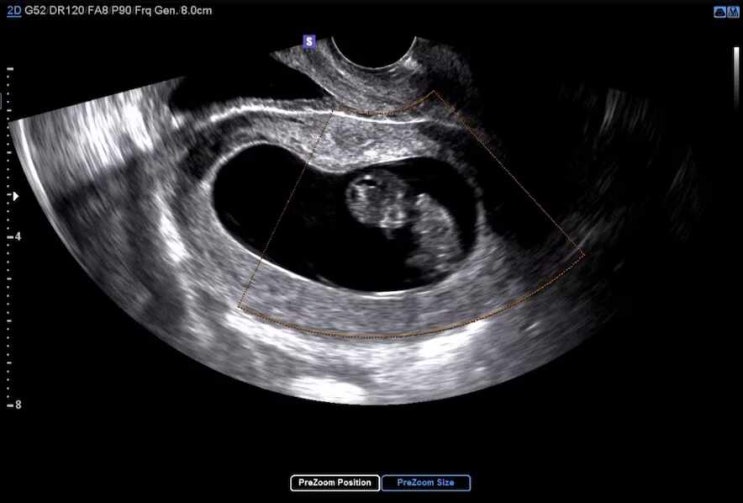

임신일기 (2월16일) ; 6주 3일차 애기 심장 본 날 + 은은한 입덧 시작

임신일기 (2월16일) 6주 3일차 애기 심장 본 날 + 은은한 입덧 시작 오늘은 임신 6주 3일차 내 포켓몬이 얼...